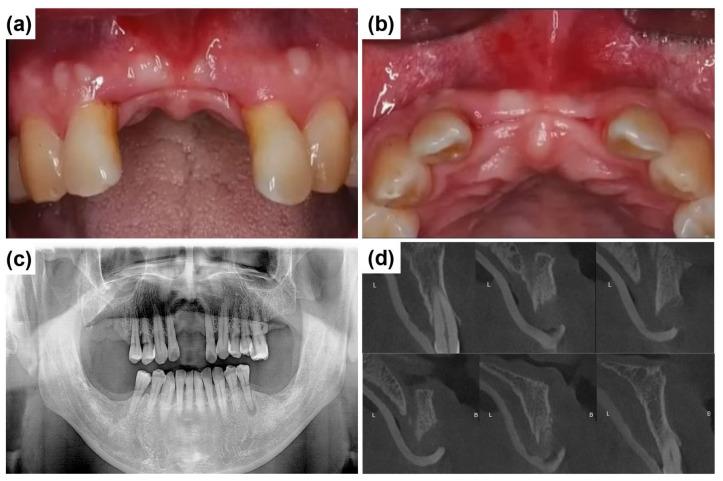

: The rehabilitation of severely resorbed anterior alveolar ridges presents significant clinical challenges due to esthetic demands and the limited bone volume in this region. Basal cortical implants, which are designed to engage dense basal bone, could offer an alternative by providing stable anchorage in compromised sites. : This report evaluates the ARi Implant System, which features cortical anchorage and a calcium-incorporated nanostructured surface (XPEED) in two anterior ridge defect cases. Soft tissue augmentation using a vascularized interpositional periosteal (VIP) flap was applied in one case, and biphasic calcium phosphate (BCP) grafting and collagen membranes were employed for ridge contouring in both cases. : At a two-year follow-up, both cases showed stable peri-implant tissues and satisfactory esthetic results. : Although basal cortical implants provide good primary stability, their use does not eliminate the need for bone augmentation, especially in the anterior esthetic region. Future clinical studies are required to substantiate long-term outcomes and broader applicability.

摘要

严重吸收的前牙牙槽嵴的修复由于美学需求和该区域有限的骨量而面临重大临床挑战。基底皮质种植体旨在与致密的基底骨结合,通过在受损部位提供稳定的锚固,可提供一种替代方案。:本报告评估了ARi种植系统,该系统在两个前牙嵴缺损病例中具有皮质锚固和含钙纳米结构表面(XPEED)。其中一例采用带血管蒂的间置骨膜(VIP)瓣进行软组织增量,两例均采用双相磷酸钙(BCP)移植和胶原膜进行嵴轮廓塑形。:在两年的随访中,两例均显示种植体周围组织稳定,美学效果满意。:尽管基底皮质种植体提供了良好的初期稳定性,但使用它们并不能消除骨增量的需求,尤其是在前牙美学区域。需要未来的临床研究来证实长期效果和更广泛的适用性。